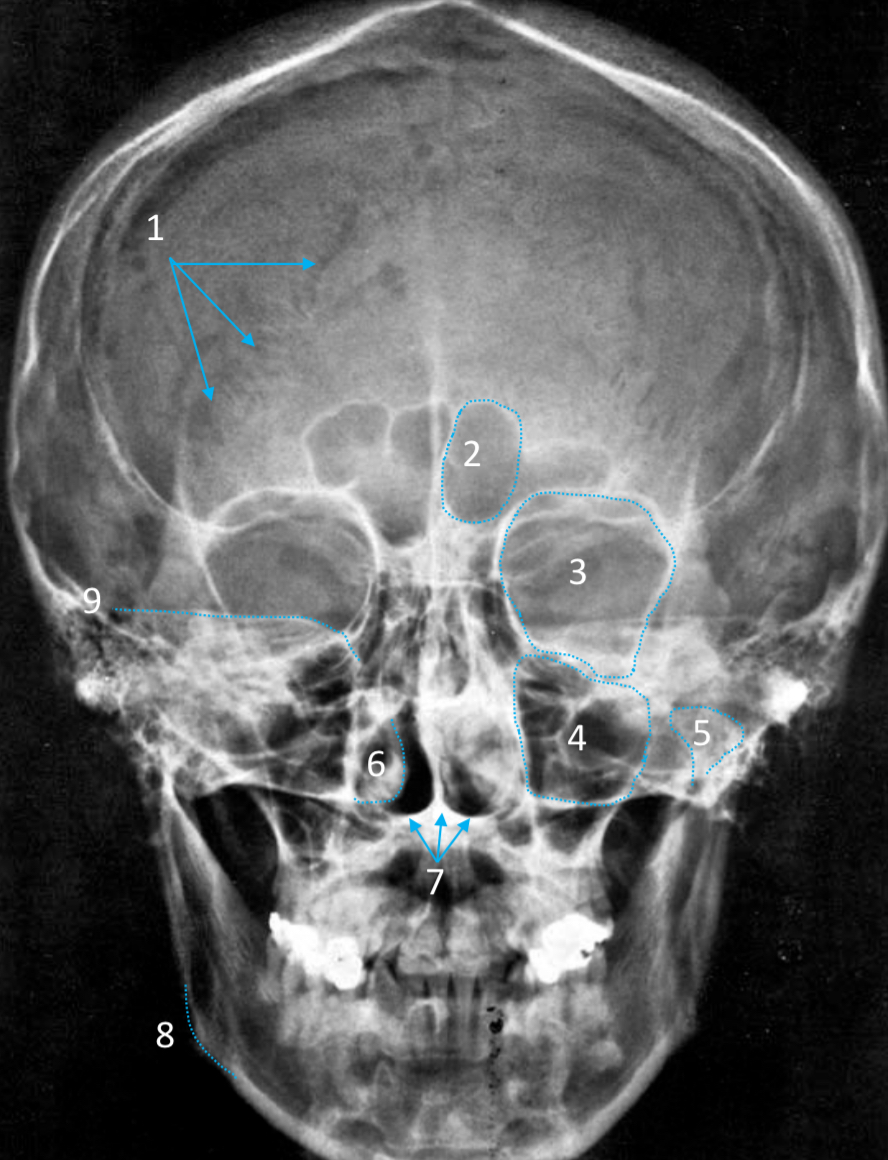

Frontal sinus

ID structure

Pituitary fossa

ID structure

Frontal sinus

ID structure

Orbital margin

Orbit

Maxillary sinus

ID structure

Mandibular condyle

ID structure

Inferior nasal concha

ID structure

Hard palate

ID strucutre

Gonial angle

ID strucutre

Petrous ridge

ID structure

Groove of middle meningeal a.

ID structure

Roof of orbit

ID structure

Frontal sinus

ID structure

Pituitary fossa

ID structure

Petrous ridge

ID structure

Sphenoid sinus

ID structure

Hard palate

ID structure

Mastoid air cells

ID structure

Zygomatic arch

ID structure

Mandibular condyle

ID structure

External auditory meatus

ID structure

Mastoid air cells

ID structure

Foramen magnum

ID structure

Foramen ovale

ID structure

Foramen spinosum

ID structure